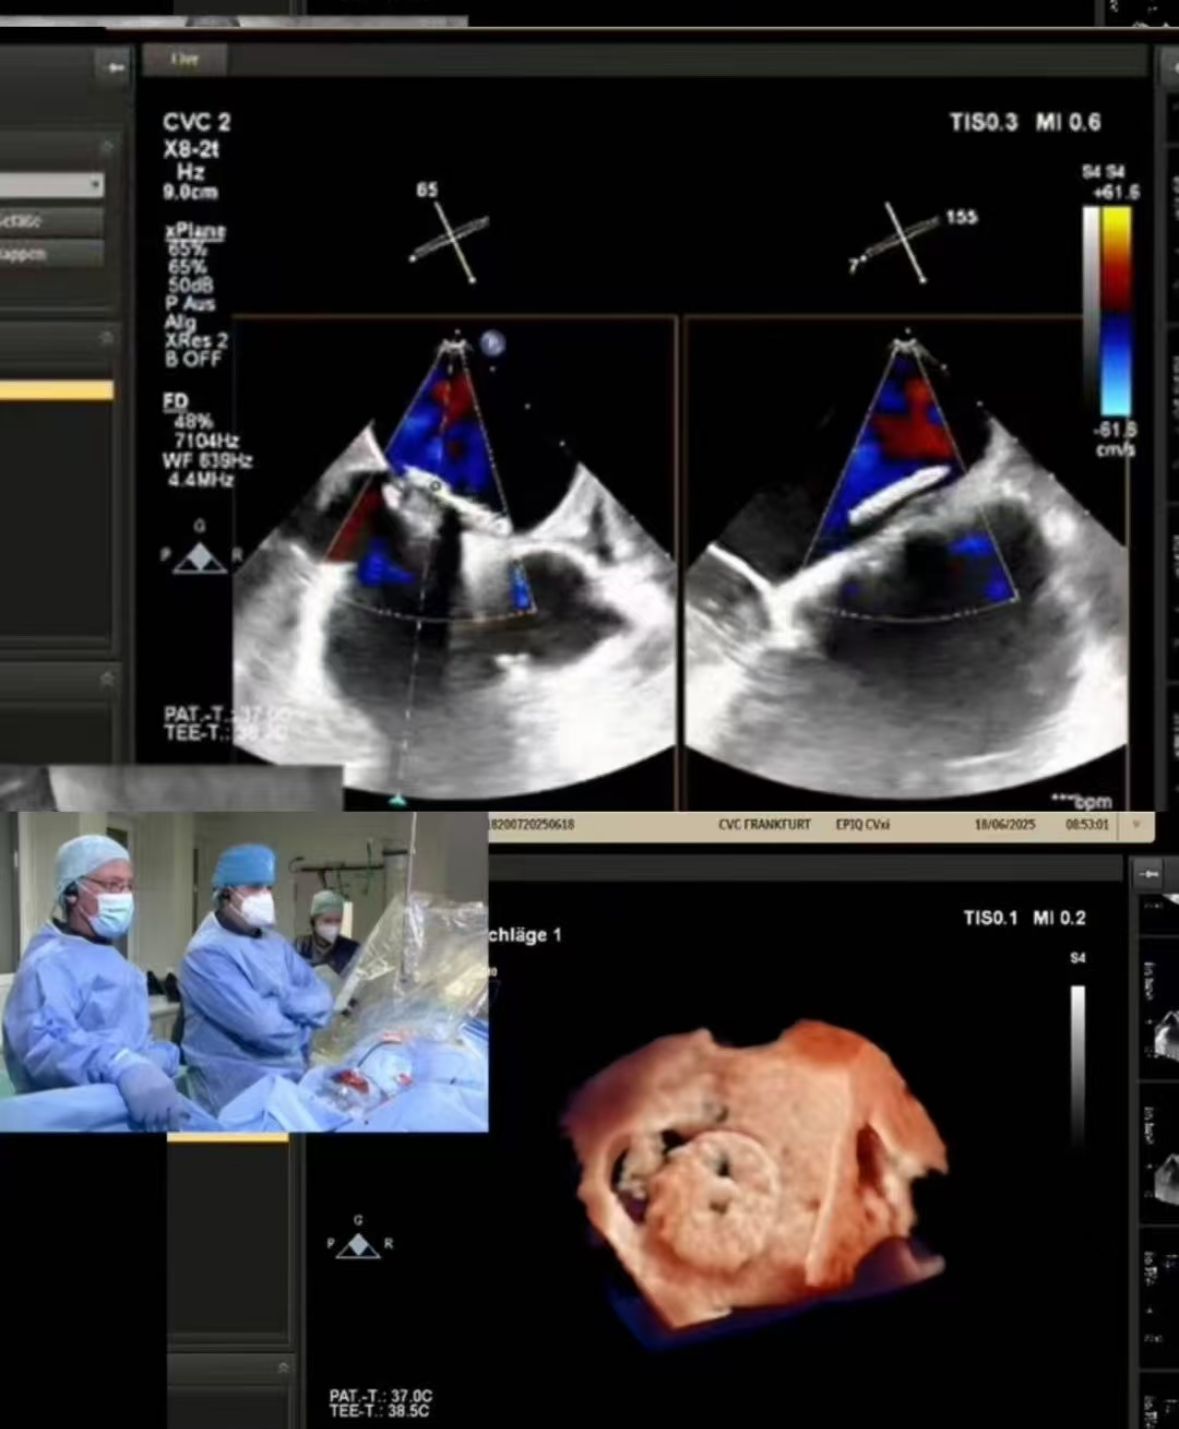

Thrilled to showcase our MemoSorb PFO Occluder – the world's first absorbable device (degrades to water & CO₂ within 1 year) – during a live broadcast from the Blue Room at CSI Frankfurt!

Abbiamo trasmesso in streaming una complessa chiusura PFO eseguita al CVC Frankfurt su una paziente di 60 anni con:

1. Corti embolici ricorrenti (2014, 2021)

2. Grave allergia al nichel (controindicazione per dispositivi metallici)

3. shunt residuo dopo la chiusura precedente

2. Chiusura precisa: l'imaging in tempo reale ha guidato la distribuzione perfetta nell'anatomia impegnativa (finestratura del tunnel PFO).